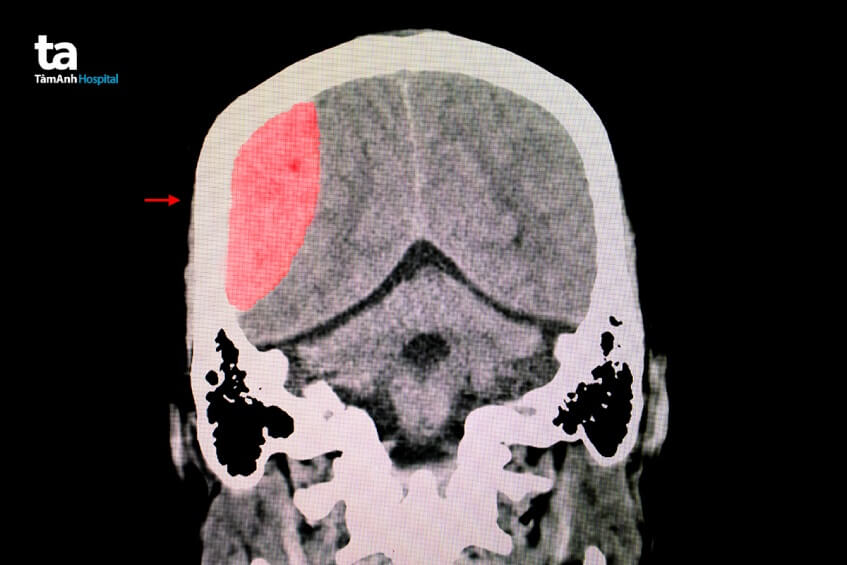

Tụ máu não là tình trạng máu bị xuất huyết trong não và tụ lại ở nhiều vị trí trong não như động mạch, tĩnh mạch, mao mạch vì một hay nhiều lý do nào đó (ví dụ khi mạch máu não bị vỡ). Nói một cách đơn giản, tụ máu não là tình trạng mạch máu bên trong não bị tổn thương, vỡ và máu chảy ra ngoài não, ứ đọng tại một vị trí nhất định.

Có 2 dạng tụ máu trong não thường gặp bao gồm: tụ máu dưới màng cứng và tụ máu ngoài màng cứng của nội sọ. Máu tụ trong não dù nằm ở vị trí nào đều cần được phát hiện sớm và điều trị kịp thời, nếu không sẽ dẫn đến nguy cơ xảy ra các biến chứng nguy hiểm như động kinh, tê liệt toàn thân, rối loạn ý thức, tử vong.

Phẫu thuật là cách điều trị tụ máu não được áp dụng phổ biến nhất. Phương pháp này thường được áp dụng khi phát hiện có máu tụ trong não tại các vị trí như: não thùy chẩm, não thất, não thùy thái dương, tiểu não, não thùy đỉnh, não thùy trán… Thông qua các kỹ thuật, máy móc hiện đại, bác sĩ có thể xác định được vị trí máu tụ trong não một cách chính xác và nhanh chóng, từ đó tiếp cận là loại bỏ khối máu tụ. (2)